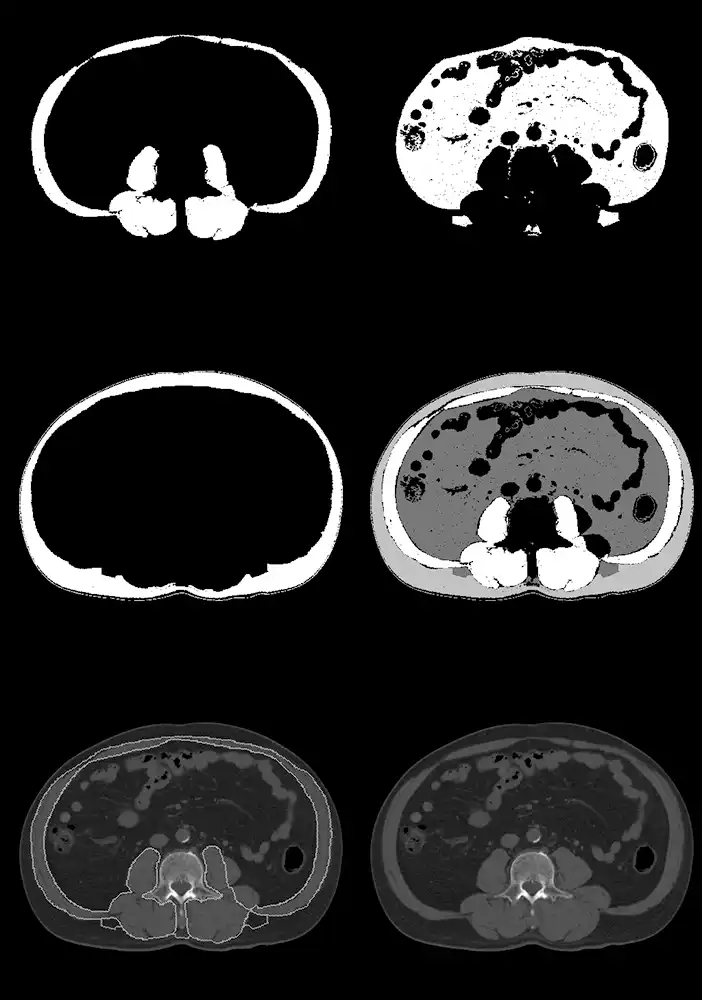

本研究室では、任意のCT画像から全自動でL3椎体中央レベルの骨格筋をセグメンテーションするツールを軸に、同レベルの内臓脂肪・皮下脂肪領域の抽出、各種統計値の抽出を行うシステムを確立しています。